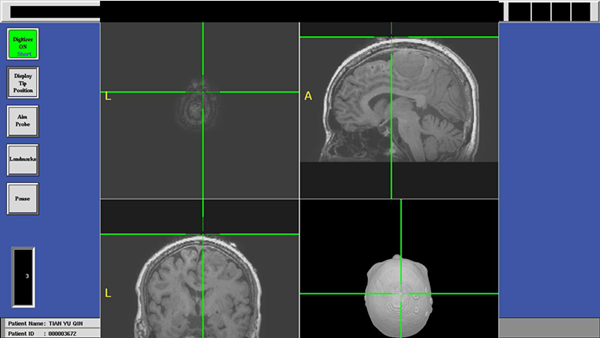

术前影像资料

术中应用导航系统进行精准定位

近年来,随着社会的发展,以及医学影像技术的进步和多种高、精、尖技术设备的发明和应用,使得神经外科快速向“精准、微创”的方向发展。微创理念的核心是:在同等疗效的前提下,尽可能保留、保护正常组织结构,从而改善术后舒适度、加速康复,是 “以人为本”的治疗理念。微创手术的实现,基于医生知识、经验、技术的积累,也依赖于先进设备的合理应用。电磁导航系统犹如“大脑里的GPS”,其为手术医生指明了一条治疗病变的“捷径”。电磁导航系统的基本工作流程、原理:术前采集影像信息并经导航系统处理,术中可应用导航探针指向颅内特定部位,在导航屏幕中便会虚拟出探针与颅内结构虚拟的三维对应关系。此功能可让手术医生清楚辨别病变与周围重要结构的毗邻关系。我院神经外科应用的导航系统为最新研发的第三代导航—电磁导航,其相对于第二代光学导航系统优势体现在:1)体积小巧,具有便携性;2)无视觉阻挡;3)不需要参考环;4)导航精确平均影像匹配误差仅1.5-2mm;5)设备兼容性良好,不影响术中应用的其他设备的正常使用。